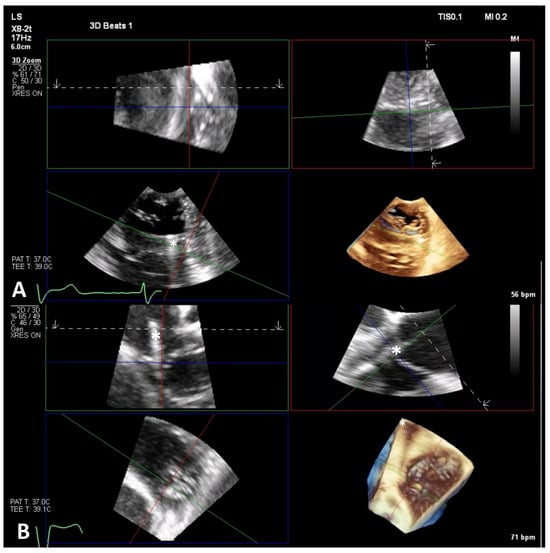

6.1. TEE-Guided Tricuspid TEER